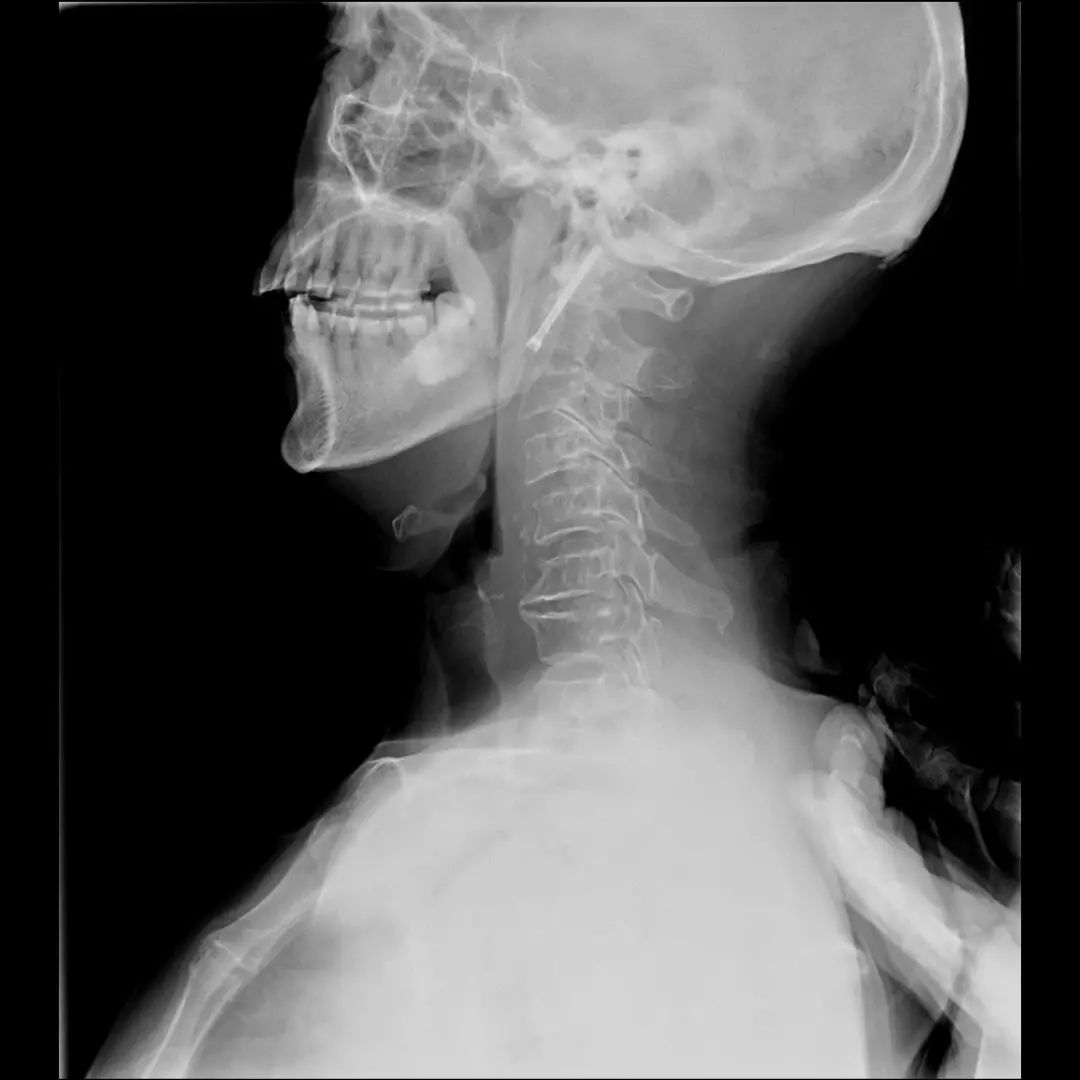

患者,男性,75岁,因外伤致颈部疼痛伴活动受限7天入院。患者入院前在当地医院确诊为:枢椎齿状突骨折Anderson-D’Alonzo分型Ⅱ型。

对于本患者来说,齿状突骨折后导致寰枢椎不稳,极易引起延髓或椎动脉损伤,严重者当场死亡。但患者同时合并严重胸腰椎后凸畸形,颈部后伸受限,不具备前路手术条件,这就给其治疗更增加了额外的困难。而由于手术部位延髓及椎动脉等血管神经密布,手术难度高、风险极大,稍有不慎,患者就会有生命危险。而患者家属在了解到手术的危险性后,曾自行到上级医院咨询专家,上级医院专家考虑围手术期死亡的风险,对于本例患者亦不愿提供手术治疗的机会。

经过全程监护和系统治疗,患者术后恢复良好,骨折解剖复位,复查X线及CT显示固定位置佳,术后3天下地行走,术后4天即出院回家休养。